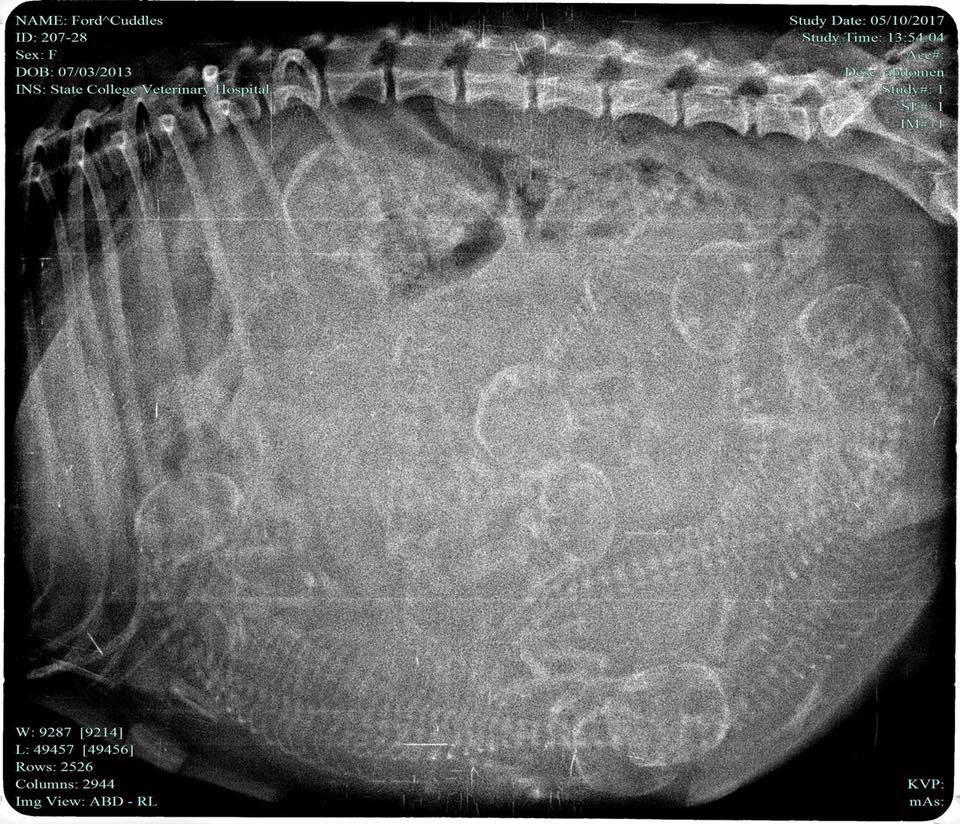

Today marks the fourth year since the passing of Buddy. We got Buddy when I was only 8 years old and he was my best friend growing up. Being an only child in a single parent family, where my dad worked 10 hour days and had two hour of computing left me only with Buddy for most of the day. He was a mixed dog that we rescued from the humane society. They were unable to tell us what he was mixed with or anything else about him. The owners dropped him and several of his brothers and sisters off at the front door of the humane society in a box with a note reading, "lease take care of these dogs, we are unable to afford to feed them?.